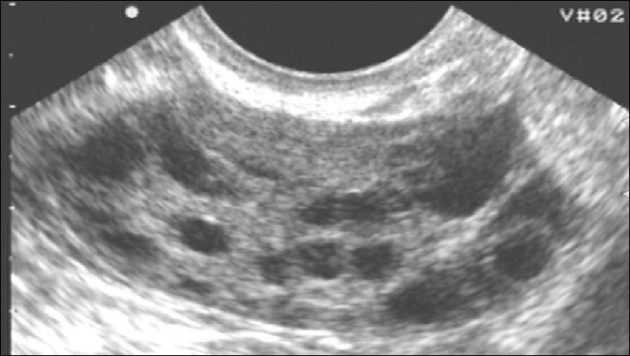

Одним из ключевых методов диагностики склерокистоза является УЗИ органов малого таза. Это исследование проводят несколькими способами с помощью разных датчиков. Трансабдоминально (через живот) можно обнаружить двустороннее увеличение размеров яичников, нередко при недоразвитой матке.

При трансвагинальном УЗИ отмечается увеличение размеров яичников свыше 9-10 см3. Определяется разросшаяся строма и недоразвитые фолликулы под утолщенной капсулой.